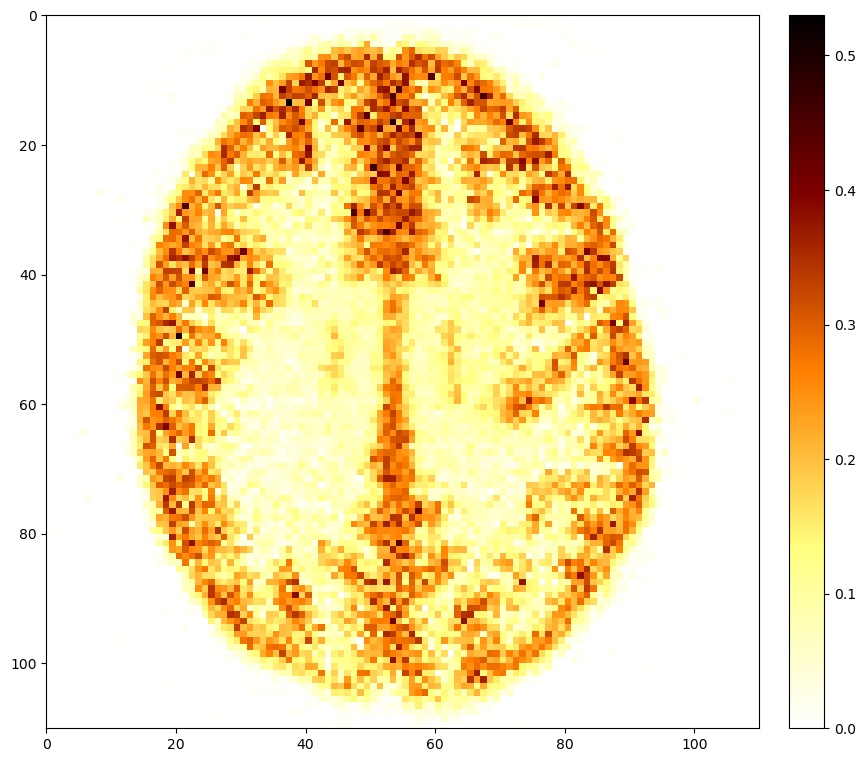

with the projection onto the non-negative image space and the average of the “sensitivity images” for each subset , a small number (determined from the OSEM image) and a step-size that decreased with iterations. This algorithm has been shown to converge to the MAP solution (ahn2003globally). Our implementation, available at GitHub:SyneRBI/SIRF-Contribs/BSREM, used a number of subsets different for each specific scanner, and manual tuning of the step size parameters. Nevertheless, we found that a high number of updates (of the order of 15 000) was often required. If necessary, the algorithm was restarted until our convergence metrics were satisfied, see section 9.5. Two reference reconstructions for test data is shown in Figure 1. A dedicated example demonstrating PET image reconstruction with BSREM using SIRF can be found in a corresponding SyneRBI notebook.

At the start of the challenge, we provided example acquired data of a small set of phantoms for participants to use for the development of their methods, complemented by further datasets during the challenge. Example test data is shown in Figure 1. An overview of the curated data is in Table 1. New data were acquired at different sites following the challenge training period, see Table 2. These data were used for scoring the performance of each algorithm. In this way the bias towards a certain vendor or scanner model was kept minimal. In addition, this approach ensured fairness of the competition because at the time of the challenge, nobody had access to the final ground truth data - including the organisers themselves.